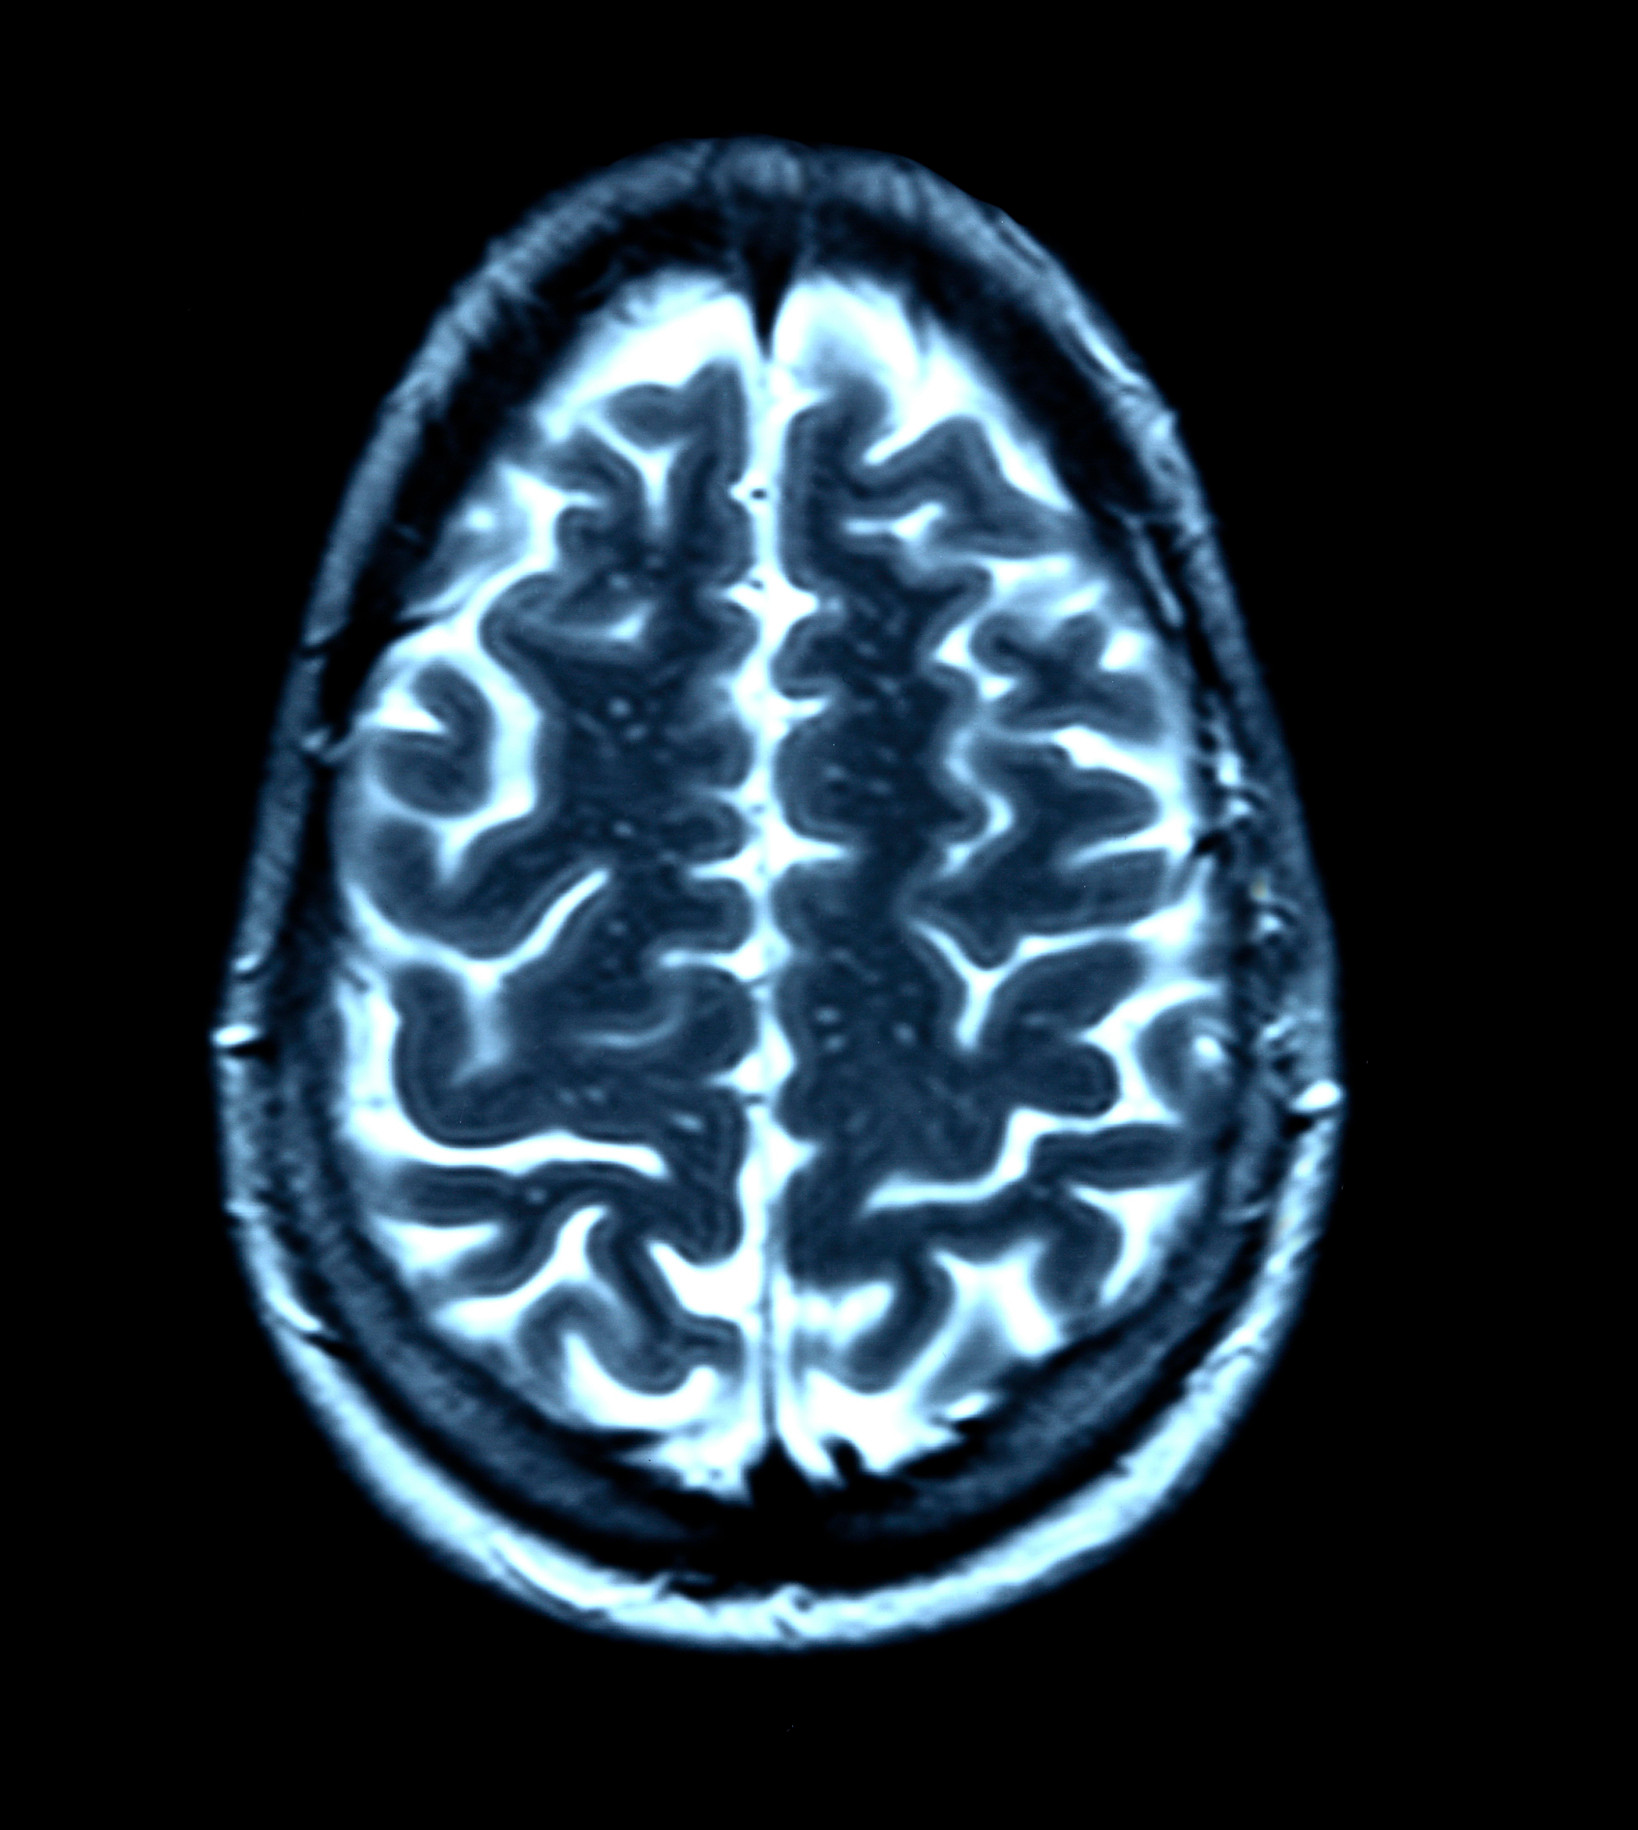

Wendepunkte des Gehirns: Was im Alter von 9, 32, 66 und 83 Jahren in unserem Kopf passiert

Wissenschaftler in Cambridge gehen von fünf Phasen der Hirn­entwicklung aus. Jeder ordnen sie spezifische Stärken und Eigenheiten zu.